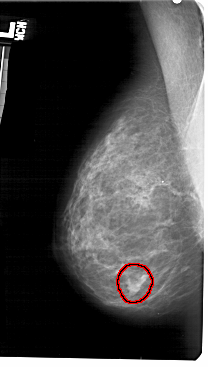

A_1362_1.LEFT_MLO

FILE: A_1362_1.LEFT_MLO.OVERLAY

TOTAL_ABNORMALITIES 1

ABNORMALITY 1

LESION_TYPE MASS SHAPE IRREGULAR MARGINS ILL_DEFINED

ASSESSMENT 4

SUBTLETY 5

PATHOLOGY BENIGN